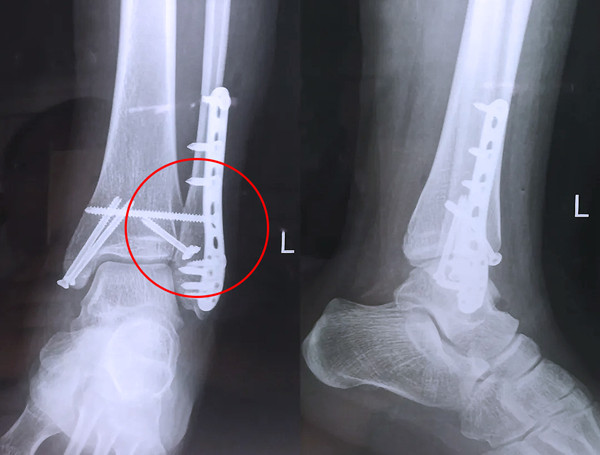

踝關(guān)節(jié)骨折在X影像上的表現(xiàn)有很多種。如內(nèi)踝骨折和外踝骨折,我們可以在影像上看到骨折處的骨折線是不連續(xù)的。還有后踝的骨折,內(nèi)踝、外踝、后踝聯(lián)合在一起發(fā)生的骨折,我們稱之為“三踝骨折”,這些都是在X影像上能夠顯示出來的。

內(nèi)踝骨折

外踝骨折

后踝骨折

三踝骨折